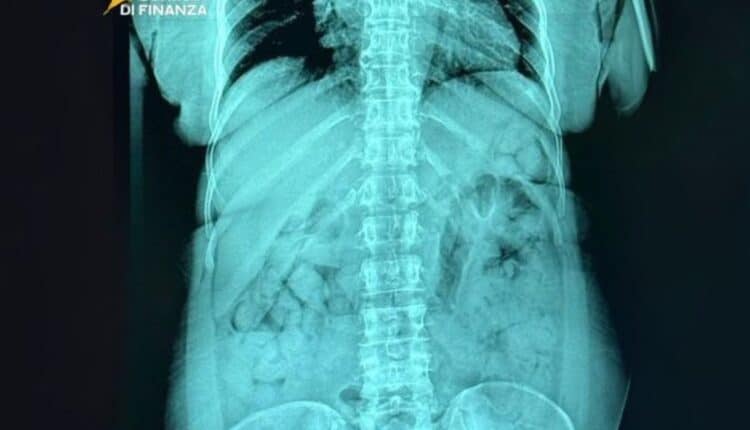

I successivi esami radiologici svolti presso l’ospedale “Papa Giovanni XXIII” di Bergamo hanno confermato che la viaggiatrice aveva ingerito 120 ovuli in contenitori plastici rigidi avvolti in strati di nastro adesivo i quali, una volta analizzati, sono risultati contenere sostanza stupefacente del tipo eroina, per complessivi 1.393 grammi.